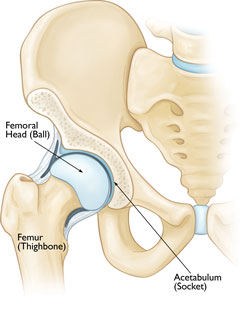

The hip is a "ball-and-socket" joint. The rounded head of the femur easily fits into the cup-shaped acetabulum to allow for a wide range of motion.